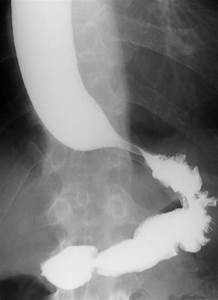

Achado típico na esofagografia baritada da acalásia

Sinal do bico de pássaro / chama de vela

Como se encontra a esofagomanometria na acalásia

Hipertonia do EEI (>35mmHg)

Perda de relaxamento fisiológico do EEI

Peristalse anormal

O que é a acalásia?

Destruição dos plexos mioentéricos de Auerbach que controlam o EEI, gerando um não relaxamento do esfincter

Isso gera uma hipertonia do esfíncter (>35mmHg) e uma peristalse anormal

Disfagia, regugirtação, halitose, pneumonia broncoaspirativa, perda de peso